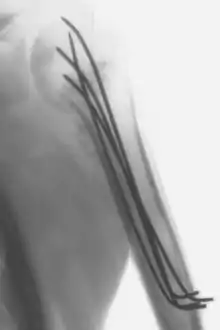

Intraoperative X-ray of a humerus fixated by Kirschner wires

Kirschner wires or K-wires or pins are sterilized, sharpened, smooth stainless steel pins. Introduced in 1909 by Martin Kirschner, the wires are now widely used in orthopedics and other types of medical and veterinary surgery. They come in different sizes and are used to hold bone fragments together (pin fixation) or to provide an anchor for skeletal traction. The pins are often driven into the bone through the skin (percutaneous pin fixation) using a power or hand drill. They also form part of the Ilizarov apparatus.